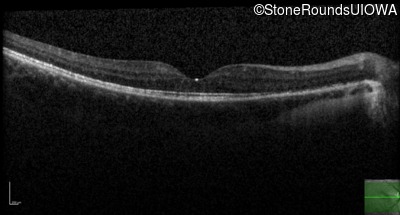

Optical Coherence Tomography - Right - 20/40 +1

Exemplar / OCT Stack